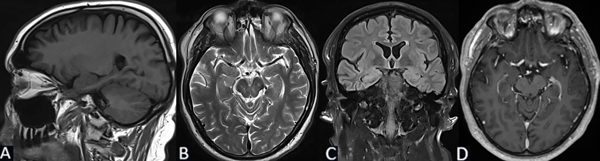

Se solicita RM cerebral con contraste, de cortes finos, donde se evidencia en secuencia T1 imagen de aspecto globuloso en la región hipocampo amigdalina paramediana derecha, ligeramente hipointensa de 2.7 x 2.5 x 1.3 cm. En T2 se comporta como hiperintensa, sin efecto de masa, sin edema perilesional. No presenta cambios posteriores a la inyección del medio de contraste (Figura 2).

Figura 2. Caso 2: RM de cerebro. A) Secuencia T1. Corte sagital. B) Secuencia T2. Corte axial. C) Secuencia T2 “TIRM Dark Fluid”. Corte coronal. D) Secuencia T1 con contraste. Corte axial.